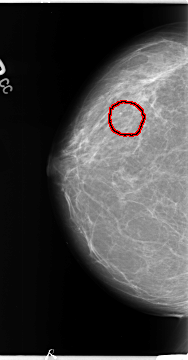

B_3121_1.RIGHT_CC

RIGHT_CC LINES 4672 PIXELS_PER_LINE 2440 BITS_PER_PIXEL 12 RESOLUTION 50 OVERLAY

FILE: B_3121_1.RIGHT_CC.OVERLAY

TOTAL_ABNORMALITIES 1

ABNORMALITY 1

LESION_TYPE CALCIFICATION TYPE PLEOMORPHIC DISTRIBUTION CLUSTERED

ASSESSMENT 4

SUBTLETY 3

PATHOLOGY BENIGN

TOTAL_OUTLINES 1

BOUNDARY